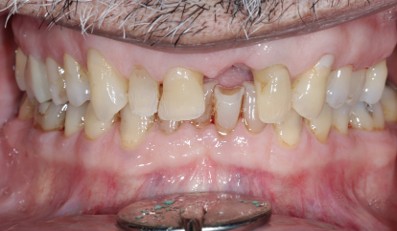

Prosthodontics (also known as dental prosthetics or prosthetic dentistry) is one of the nine dental specialties recognized by the American Dental Association (ADA). Prosthodontists specialize in the diagnosis, restoration, and replacement of missing teeth.

Extensive training and experience give prosthodontists a unique understanding of restoring the dynamics of a smile and healthy mouth with the creation of tooth prostheses. Becoming a prosthodontist requires an additional three years of specialty training after obtaining a DMD (Doctor of Dental Medicine) or DDS (Doctor of Dental Surgery) degree.